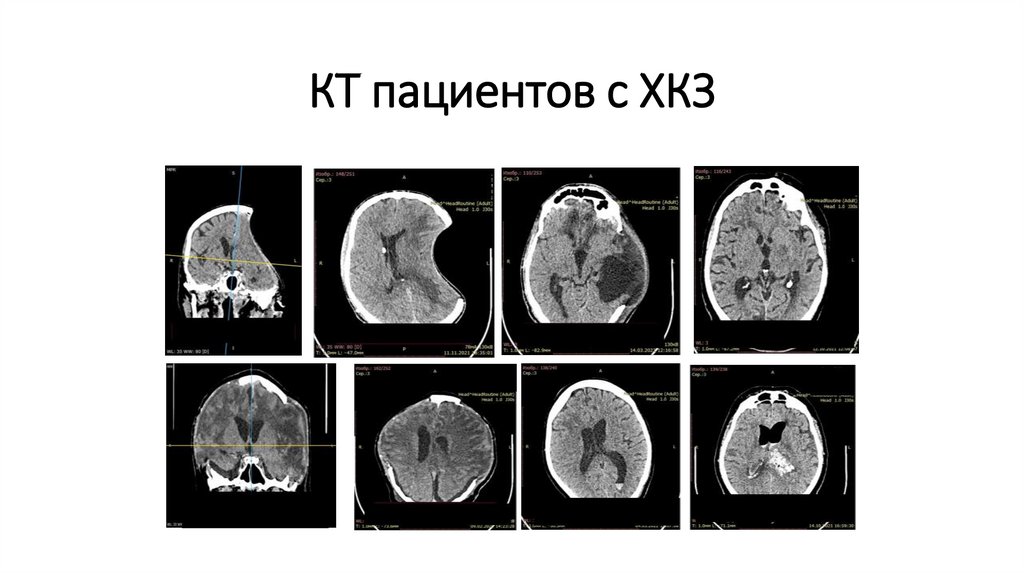

КТ пациентов с ХКЗ

67. КТ пациентов с ХКЗ